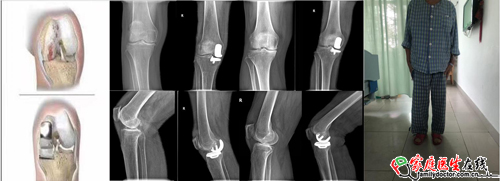

“以前听说膝骨关节炎需要手术做全膝关节置换,要不就长期吃药,没想到还能做微创,效果好还省了不少钱”患者彭女士(化名)说。